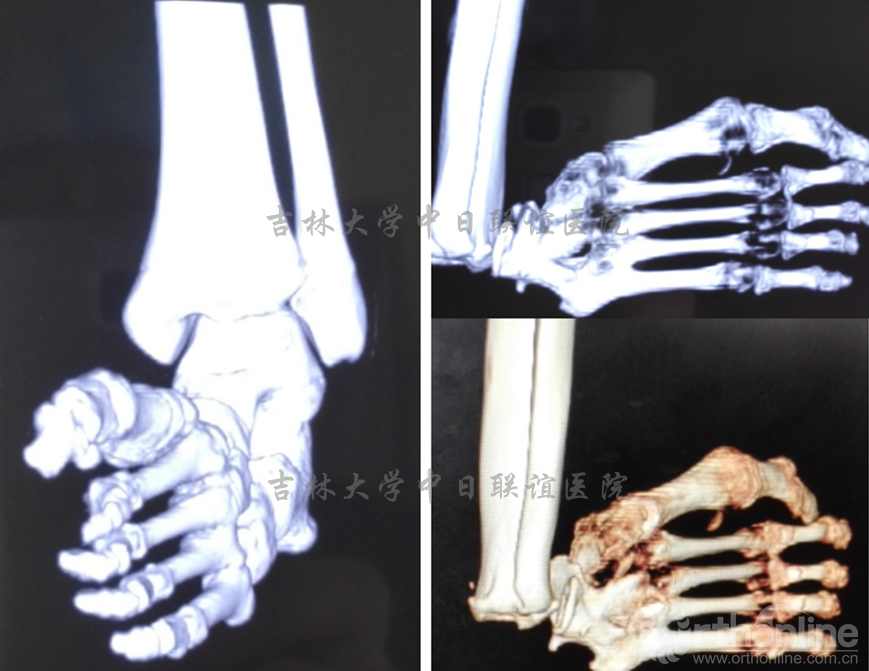

脊柱短缩截骨术后1年后行双足畸形矫形术:术后1年,患者双下肢感觉、肌力明显好转。一期右足行皮肤软组织松解覆盖创面3月后二期行矫形手术治疗。

影像学检查及外相: